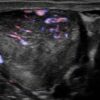

U tinh hoàn

» Thông tin: Nam giới – 35 tuổi.

» Lâm sàng: Sưng tinh hoàn.

# U tinh bào (Seminoma).